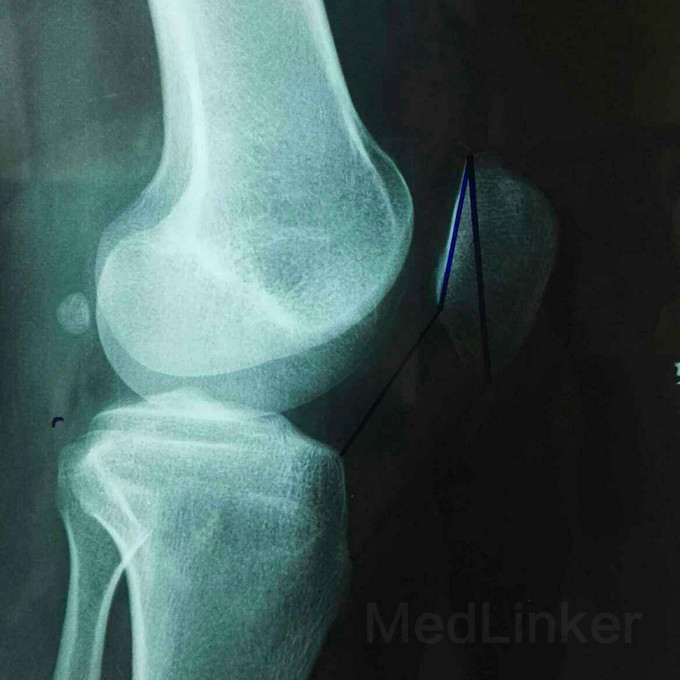

患者女,19岁,双膝关节习惯性髌骨脱位10余年,多家医院建议手术治疗,2个月前摔伤致左髌骨脱位,于某院行手术治疗,经家人商讨后决定再行右膝手术治疗来我院。请老师们指点是否需要调整髌骨远端力线?做何手术最为简单有效?具体是做单纯外侧支持带松解?外侧支持带松解+内侧关节囊缩紧筋膜成形?外侧支持带松解+髌腱手术?外侧支持带松解+胫骨结节内移?还是外侧松解+内侧紧缩成形+胫骨结节内移?还是什么?